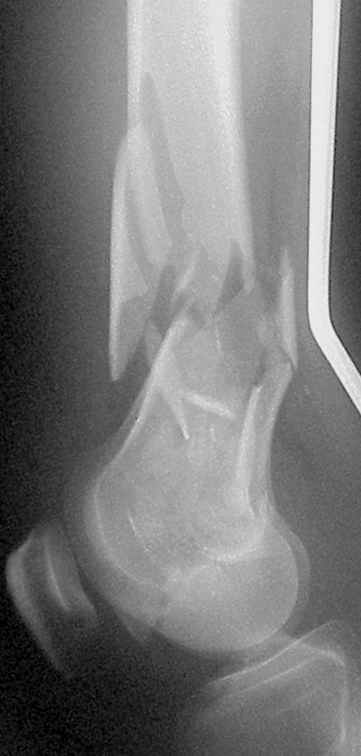

- Left tibia fracture (41-A3.3) closed

- Right femur fracture (33-C3.3) open grade III-A

On Thersday afternoon he was alright, he is a very active man and he was moving well both knees. Later that evening he told me that while he was a little bit asleep he turned on the bed and felt pain and that the femur was loose. Here are the X-rays we took.